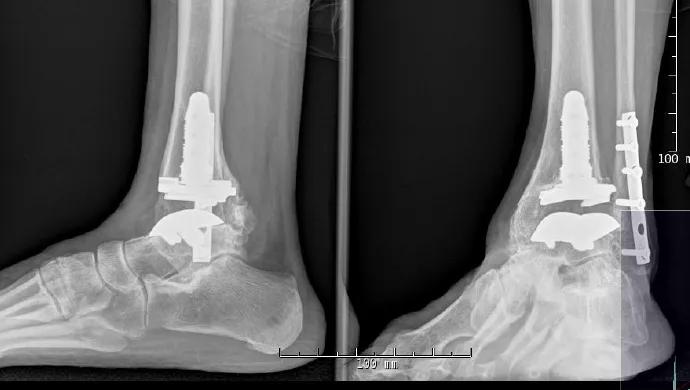

Total Ankle Replacement for End-Stage Arthritis

Ankle fusion or total ankle replacement (TAR)? It’s one of the biggest dilemmas faced by patients with end-stage ankle arthritis and their orthopaedic surgeons. Ankle arthrodesis has been the gold standard, but development of both radiographic and clinically relevant degenerative disease in the adjacent joint at long-term follow-up has made TAR an attractive option in appropriate patients. For patients requiring bilateral ankle fusions or those with end-stage ankle arthritis and previous hindfoot or midfoot fusions, studies demonstrate that ankle fusions have unfavorable effects on gait and functional capability.

First-generation ankle replacements, which required cemented fixation and significant bone resection, were hindered by high complication and failure rates. Renewed interest in more anatomically based, cementless designs spurred development of second- and now third-generation implants, which have demonstrated improved results at short- and medium-term follow-up. The hallmarks of third-generation implants are cementless fixation, with minimal bone resection as a result, and a polyethylene articulation. Outcomes, in terms of pain scores, range of motion and patient-rated functional capacity, have been promising with newer-generation designs.1

What Cleveland Clinic Uses

Of the several FDA-approved TAR implant systems, Cleveland Clinic currently uses the following three: • The Scandinavian Total Ankle Replacement System (STAR™ Ankle, Small Bone Innovations) is the only FDA-approved cementless, three-piece, mobile-bearing implant. One of the proposed benefits of this system is the limited bone resection needed for implantation, which should make future conversion or revision more feasible if necessary. Five- and 10-year implant survival rates as high as 90 percent and 80 percent, respectively, have been reported.2 The mobile-bearing system increases the planes of motion, allowing some varus and valgus tilt in the mortise during ambulation. • The Inbone® Total Ankle System (Wright Medical Technology) is a modular, fixed-bearing, two-component system with intramedullary tibial and talar components. The modularity allows different-sized tibial and talar components to be used to match the patient’s native anatomy. Preoperative CT scans can be used to fabricate preoperative navigation alignment guides to serve as patient-specific instruments to assist in intraoperative positioning of the TAR components. These guides also allow the surgeon to avoid use of the Inbone leg holder intraoperatively, which can be very helpful in the OR. This system works well for primary cases as well as revisions. • The Salto Talaris™ Total Ankle Prosthesis (Tornier) has a design and instrumentation founded on the Salto mobilebearing ankle prosthesis, which has been in clinical use in Europe since 1997. Studies demonstrate greater than 90 percent implant survival at midterm follow-up.3 A key principle of this system is that the mobile-bearing concept has been moved from the final implant into the stage of trialing instrumentation. Specifically, the trial tibial base is allowed to rotate into proper position by moving the ankle through an arc of motion, thus allowing the prosthesis to self-align. The tibial keel preparation is then completed, essentially locking the components into their appropriate positions. The Trabecular Metal™ Total Ankle (Zimmer) was recently approved in the U.S. but has not yet been implanted at our institution. It is a semiconstrained device with three implant components designed to be implanted via a lateral malleolus osteotomy.

At Cleveland Clinic, we consider many factors when choosing whether to perform ankle fusion or TAR ‒ and then, if TAR is pursued, which implant to use. The patient’s weight, age, angular deformity, soft tissues and activity level are all considered. The aim is to match these patient characteristics to the implant system in order to minimize soft tissue dissection and bone resection and preserve the ankle’s natural anatomy and kinematics.